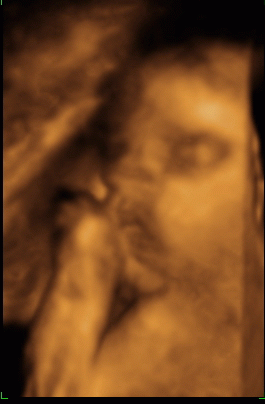

A picikémmel nem tudom mi van, ficereg a drágám, de majd bővebben 10-én megtudom, hogy minden rendben van-e odabenn vele, akkor megyek 4D UH-ra! Hát remélem a legjobbakat!

Íme egy képecske róla a 28. héten készült, és szép nagyra nőtt, majdnem 2 héttel nagyobb a koránál: Kép